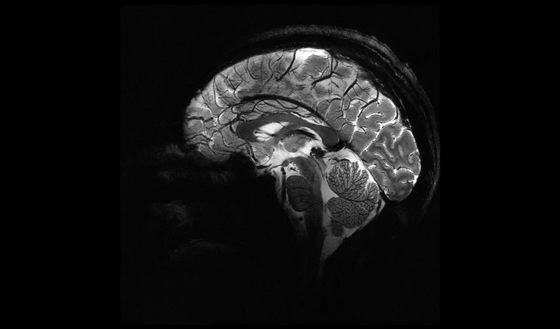

Jelentős felfedezést tettek magyar kutatók az emberi agy egyik legfontosabb részéről

A HUN-REN Kísérleti Orvostudományi Kutatóintézet kutatói fontos sejtcsoportokat határoztak meg az emberi hippokampusz különböző rétegeiben. Eredményeik olyan betegségek kutatásában bírhatnak nagy jelentőséggel, mint a skizofrénia, az epilepszia és az Alzheimer-kór.